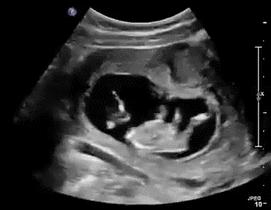

还记得胎宝宝第一次和你打招呼的惊喜吗?

胎儿在子宫内的活动称胎动,进入孕晚期,您是怎么数胎动的呢?其实每个宝宝都有TA的脾气…

胎动监测是孕妇自我评价胎儿宫内状况的简便经济的有效方法。一般妊娠20周开始自觉胎动,胎动夜间和下午较为活跃。正常胎动每小时3~5次,随着孕周的增加逐渐增强,至妊娠32~34周达高峰,妊娠38周后因羊水量减少而胎动减弱。